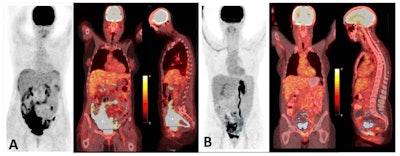

An example of two different patients with high and low tumor burden. (A) A 54-year-old patient with HGSOC; MTVtotal: 1,204 cm3, MTVtarget: 1,186 cm3, TLGtarget: 3768.6 mL × cm3, and TLGtotal: 3777.4 mL × cm3. DFS= 4 months. (B) A 50-year-old patient with HGSOC; MTVtotal: 194.8 cm3, MTVtarget: 152 cm3, TLGtarget: 542.6 mL × cm3, and TLGtotal: 261.2 mL × cm3. DFS = 44.9 months. Image and caption available for republishing under Creative Commons license (CC BY 4.0 DEED, Attribution 4.0 International) and courtesy of Cancers.

According to the results, the median disease-free survival (DFS) was 18 months, and overall survival was 33.6 months, and MTV was significantly associated with DFS. Specifically, patients with an MTVtotal greater than 427.8 cm3 and an MTVtarget greater than 434 cm3 on the images had shorter DFS than patients with lower values (18.8 vs. 31 months and 15.6 vs. 30 months).

In addition, patients with higher TLGtotal and TLG(t) values on F-18 FDG-PET/CT also tended to have worse DFS and MTVtotal was statistically significantly associated with DFS, the group reported.